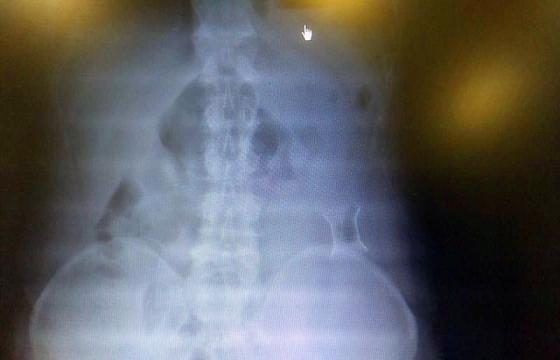

受試患者在結(jié)腸端端吻合術(shù)中,使用我司新研制產(chǎn)品達(dá)到了理想的預(yù)期效果?;颊咝g(shù)后7天、14天X光片顯影,可降解腸道支架均能按研制設(shè)計的預(yù)期時間節(jié)點保持應(yīng)有強度,術(shù)后21天X光片顯示可降解腸道支架已完全破碎,并排出體外。在整個試驗過程中,病患無任何不良反映,耐受良好。